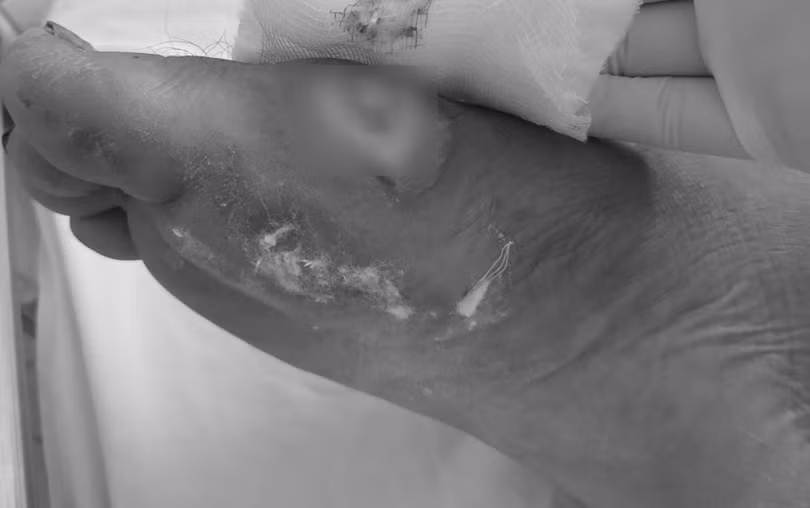

Bàn chân một bệnh nhân bị vi khuẩn Burkholderia pseudomallei làm hoại tử. Ảnh: Bệnh viện cung cấp.

Bác sĩ chuyên khoa 2 Phạm Ngọc Hàm, Trưởng khoa Y học nhiệt đới, Bệnh viện Đà Nẵng, nói rằng nhiều người hoang mang, đồn đoán về căn bệnh Whitmore, gọi là bệnh do vi khuẩn ăn thịt người. Thực chất, bệnh Whitmore, còn gọi Melioidosis, là do nhiễm vi khuẩn Burkholderia pseudomallei sống trong môi trường tự nhiên. Bệnh dẫn đến tình trạng áp xe, hoại tử nhiều cơ quan, trong đó có da. Còn vi khuẩn “ăn thịt người” là loại khuẩn khác .

Tuy nhiên, bệnh tiến triển rất nghiêm trọng, tỷ lệ tử vong cao, đặc biệt với những người đang mắc bệnh mạn tính. Mức độ nghiêm trọng của bệnh dựa vào tình trạng nhiễm trùng. Người bị tiểu đường, bệnh phổi mạn tính, bệnh thận mạn tính và ung thư, nguy cơ tử vong cao hơn khi nhiễm vi khuẩn này.